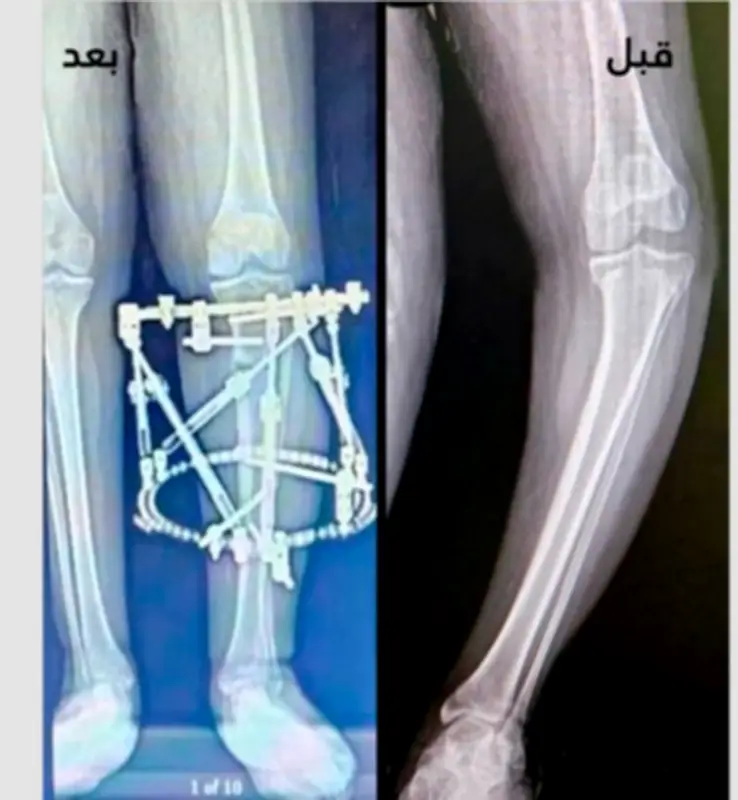

في إنجاز طبي متميز، نجح فريق متخصص في جراحة العظام بمدينة الملك سلمان الطبية بالمدينة المنورة في إجراء عملية جراحية دقيقة ومعقدة لعلاج حالة تقوس شديد ودوران داخلي بساق شاب يبلغ من العمر 17 عامًا. العملية التي استخدمت تقنية متطورة ساهمت في استعادة استقامة الطرف السفلي للشاب بشكل كامل، مما أعاد له القدرة على المشي الطبيعي وممارسة أنشطته اليومية والرياضية دون معاناة من الألم.

أجرى الفريق الطبي عملية قص عظمي دقيقة أعلى عظمة القصبة اليسرى للشاب، والتي كانت تعاني من تشوه حاد نتيجة التقوس والدوران الداخلي. تم استخدام جهاز تثبيت خارجي حلقي متطور خلال العملية، وهو جهاز يسمح بتثبيت العظام وتصحيح وضعها تدريجيًا وبشكل مضبوط. هذا النهج الجراحي ساهم في تصحيح الانحناء واستعادة المحاذاة الطبيعية للساق، مما أدى إلى تحسين وظيفة الطرف السفلي بشكل ملحوظ.

بعد نجاح العملية، تمكن الشاب من استعادة قدرته على المشي بشكل طبيعي وفعال، وهو ما كان يمثل تحديًا كبيرًا له سابقًا بسبب الألم والتشوه. كما أتاحت النتائج الإيجابية للعملية للشاب العودة إلى ممارسة حياته اليومية المعتادة والأنشطة الرياضية التي كان يحبها، دون أي قيود أو آلام. هذا الإنجاز الطبي يسلط الضوء على التقدم الكبير في مجال جراحة العظام والتقنيات الحديثة المستخدمة في علاج الحالات المعقدة.